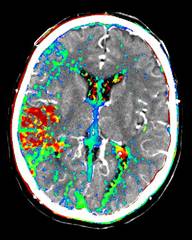

• Kontrastmittelgestützte Perfusionsbildgebung des Gehirns mittels MRT und CT.

• Entwicklung und Evaluierung neuer Berechnungsmethoden für PWI Parameterbilder.

• In Zusammenarbeit mit der Neurologischen Klinik: Verlaufskontrolle bei neuen Therapieansätzen.

• Volumetrische Auswertungen von PWI-Parameterbildern: "DWI - PWI Mismatch-Konzept".